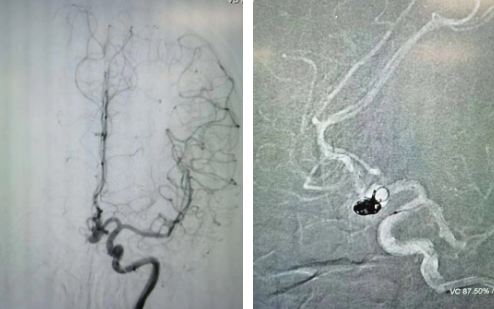

經(jīng)過(guò)全面仔細(xì)評(píng)估,西安國(guó)際醫(yī)學(xué)中心醫(yī)院神經(jīng)外科陸丹醫(yī)生決定采用微創(chuàng)介入進(jìn)行治療。在取得患者及家屬同意后,3月11日,陸丹醫(yī)生為患者行Atlas支架輔助顱內(nèi)動(dòng)脈瘤栓塞術(shù)。

腦血管較外周血管更為脆弱、迂曲,對(duì)術(shù)者的操作技術(shù)及精準(zhǔn)性要求特別高。術(shù)中,陸丹醫(yī)生通過(guò)股動(dòng)脈穿刺、置入微導(dǎo)管,再通過(guò)微導(dǎo)管將彈簧圏送入動(dòng)脈瘤腔內(nèi),利用彈簧圈的機(jī)械閉塞作用,達(dá)到防止動(dòng)脈瘤破裂的目的。術(shù)后,患者各項(xiàng)生命體征平穩(wěn)。

陸丹醫(yī)生介紹,此次腦科醫(yī)院首次采用Atlas支架輔助進(jìn)行顱內(nèi)動(dòng)脈瘤栓塞術(shù)。以往動(dòng)脈瘤栓塞術(shù)中的支架輸送導(dǎo)管較粗,支架順應(yīng)性差,易使載瘤動(dòng)脈移位,而Atlas支架的輸送導(dǎo)管很細(xì),輸送順滑,同時(shí)順應(yīng)性及貼壁性強(qiáng),能夠適應(yīng)迂曲的腦遠(yuǎn)端血管。